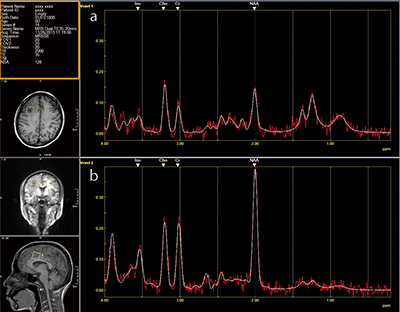

また,脳腫瘍の術前検査や質的診断を目的としたMRSを実施している。ECHELON OVALでは,“ワンクリック”による計測からLCModelソフトウエアによる解析まで簡単な操作でMRSが可能だが,黒瀬TSは,「実際に病変部と正常部に20mm×20mmのROIを置き,ワンクリック・8分間で計測が終わります。計測後のスペクトルグラフの作成まで,スムースな処理が可能です」と評価する。

■症例2:MRS

aのグラフはbのグラフに比して,NAAの値が低下している。

悪性の脳腫瘍などが考えられる。

MRSSE,TR:2000,TE:35.0,20mm isovoxel